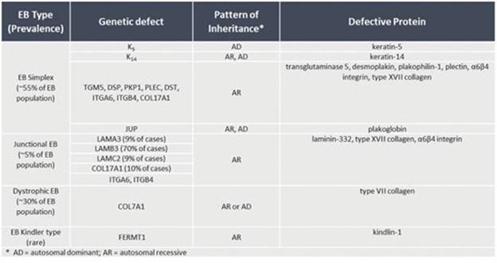

There are four main subtypes of the condition. Each of these subtypes can display a spectrum of phenotypic severity reflecting the types of mutations in different genes, together with modifying environmental factors. The types of mutations also determine the mode of inheritance, either autosomal dominant or autosomal recessive. The following table shows the pattern of inheritance and the defective genes and proteins in each:

Classification of EB Types

(a) EBS

This is the most common form of EB and is characterized by a lack of adhesion of the skin directly above the basement membrane (the basal layer). An estimated 55% of people with EB have EBS resulting from a genetic defect of the keratins K5 and K14, with the incidence between the two defects estimated to be essentially equal. The most common form of EBS manifests itself as blistering confined to the hands and feet while in others blistering can occur all over the body. Blistering generally appears during the neonatal period but it can also manifest itself in later childhood (or even in adult life). Painful skin blisters are accentuated by friction, especially on the feet where footwear causes increased irritation. Friction injuries tend to occur more commonly in warm weather and secondary infections are common.

(b) Junctional EB

Junctional EB is characterized by a lack of adhesion of the skin through the basement membrane and affects some 5% of those with EB. The generalized type of junctional disease (about half of cases of junctional EB) is usually fatal in infancy. This is often as a result of anemia and malnutrition due to poor feeding caused by the serious blistering in the pharynx and esophagus. The milder form of the disease can cause life-long pain and disability.

(c) Dystrophic EB, or “DEB”

DEB is characterized by a lack of adhesion of the skin under the basement membrane. Approximately 30% of people with EB have DEB. Patients with DEB tend to develop blisters that heal with fibrosis, leading to joint contracture, fusion of the fingers, contractures of the mouth membranes and narrowing of the esophagus. Often the dominant inherited type of DEB is the least severe type and the patient can lead an almost normal life. However, the severity of the condition does increase with age due to scarring, syndactyly and generalized skin atrophy. Those with recessive DEB have a high chance of developing a squamous cell carcinoma, often before the age of 35.

(d) Kindler Syndrome

This type of EB is rare and usually becomes apparent at birth or soon after. This condition is called mixed type because blisters appear across the skin layers. The condition usually improves with time and can disappear. It is the only type that causes patchy discoloring (mottling) of skin exposed to the sun. Kindler syndrome is recessive.